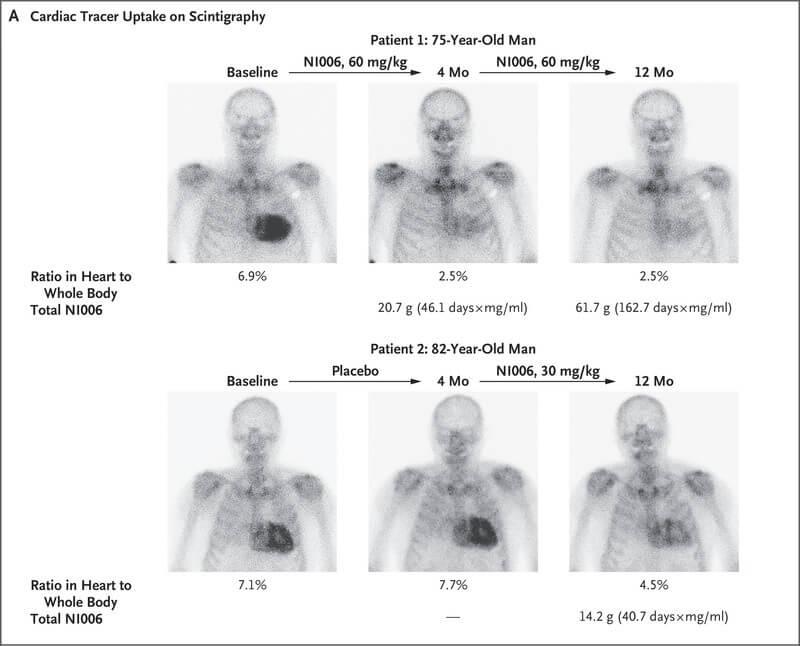

We can’t fully hang our hats on the results of a study with so few patients — but all the results they did see were encouraging. In just the initial four months of treatment, imaging scans of volunteers who got real NI006 showed that much of the amyloid that had invaded their heart muscles had been cleared out — and the amyloid continued to disappear as they continued to receive NI006 during the eight months of all-comers treatment.

By contrast, the control group suffered the expected further accumulation of amyloid as they were “treated” with salt water for the first four months. But once they got access to the real thing, their cardiac amyloid, too, began to retreat. And across the mix of placebo infusions and differently-dosed antibody treatments that different volunteers received, there appeared to be a “dose-response” effect: the more NI006 a person got, the more amyloid was cleared out of their heart.

The investigators also measured blood biomarkers of heart muscle damage in the volunteers — and while the results had a lot of noise, the data are consistent with a therapeutic effect of removing amyloid. Nothing much changed for the first four months of treatment with either NI006 or the placebo. But after an additional eight months of treatment, both markers of cardiac injury began to trend downward — and promisingly, the improvements were greatest in people who had received higher doses of NI006 from the outset. (Look at the Figure below, and compare the number of people who took NI006 from the beginning (represented by the red dots) that either hug the overall trend line or are even below it, versus how many who were originally on placebo who had to wait until the extension phase to get NI006 (the yellow dots) and are above the trend line, with many having enjoyed no reduction in damage markers at all).